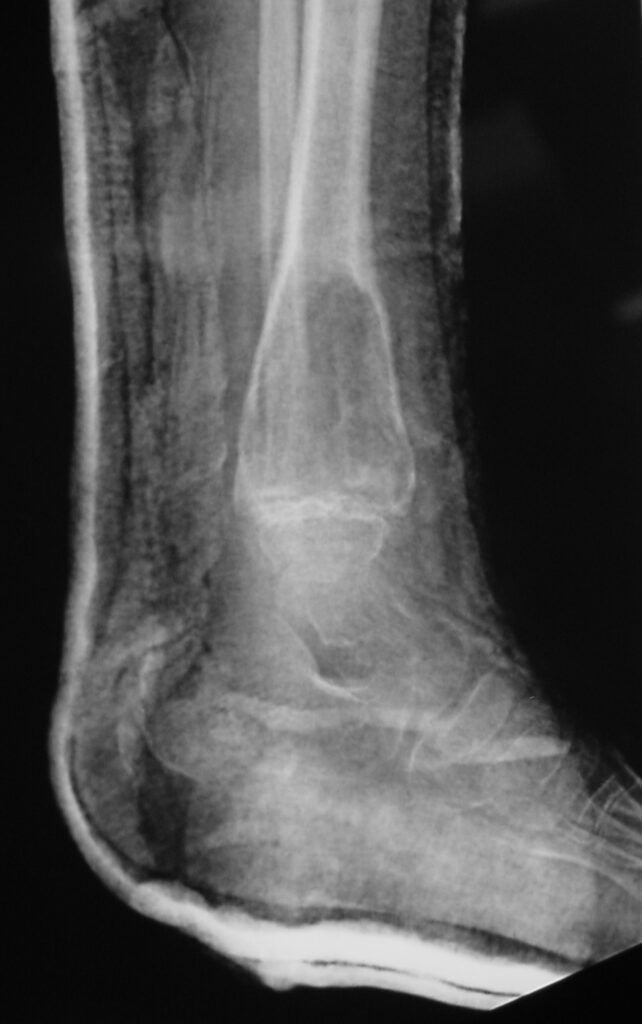

Fig 1a. Plain X-ray (AP View). ABC of the Distal Tibia: Geographic Well Circumscribed Lesion in the distal tibia. The cortices are expanded. There are internal septations. There is no internal mineralization. There is no evidence of a malignant appearing periosteal reaction such as a sunburst or hair on end pattern or codman’s triangle.

Fig 1b: Plain X-ray (Lateral View): ABC of Distal Tibia. Notice how the cortices or bony contour appears expanded. The tumor has been eroding the inner aspect of the cortex of the bone. In response the periosteum on the outside lays down new bone which gives the bone and expanded contour.